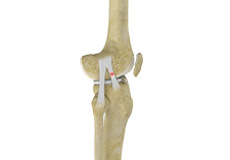

Ligaments of the Knee

Ligaments are tough bands of tissue that connect one bone to another bone. The ligaments of the knee stabilize the knee joint. There are two important groups of ligaments that hold the bones of the knee joint together, collateral and cruciate ligaments.

Collateral ligaments are present on either side of the knee. They prevent the knee from moving too far during side to side motion. The collateral ligament on the inside is called the medial collateral ligament (MCL) and the collateral ligament on the outside is called the lateral collateral ligament (LCL).

Cruciate ligaments, present inside the knee joint, control the back-and-forth motion of the knee. The cruciate ligament in the front of the knee is called anterior cruciate ligament (ACL) and the cruciate ligament in the back of the knee is called posterior cruciate ligament (PCL).